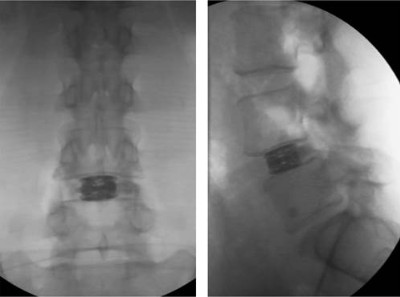

Control radiológico final del implante expandido